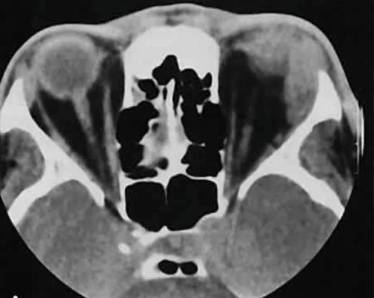

Диагностика:

- лабораторные исследования крови и тканей из ран;

- рентген позвоночника;

- МРТ;

- КТ.